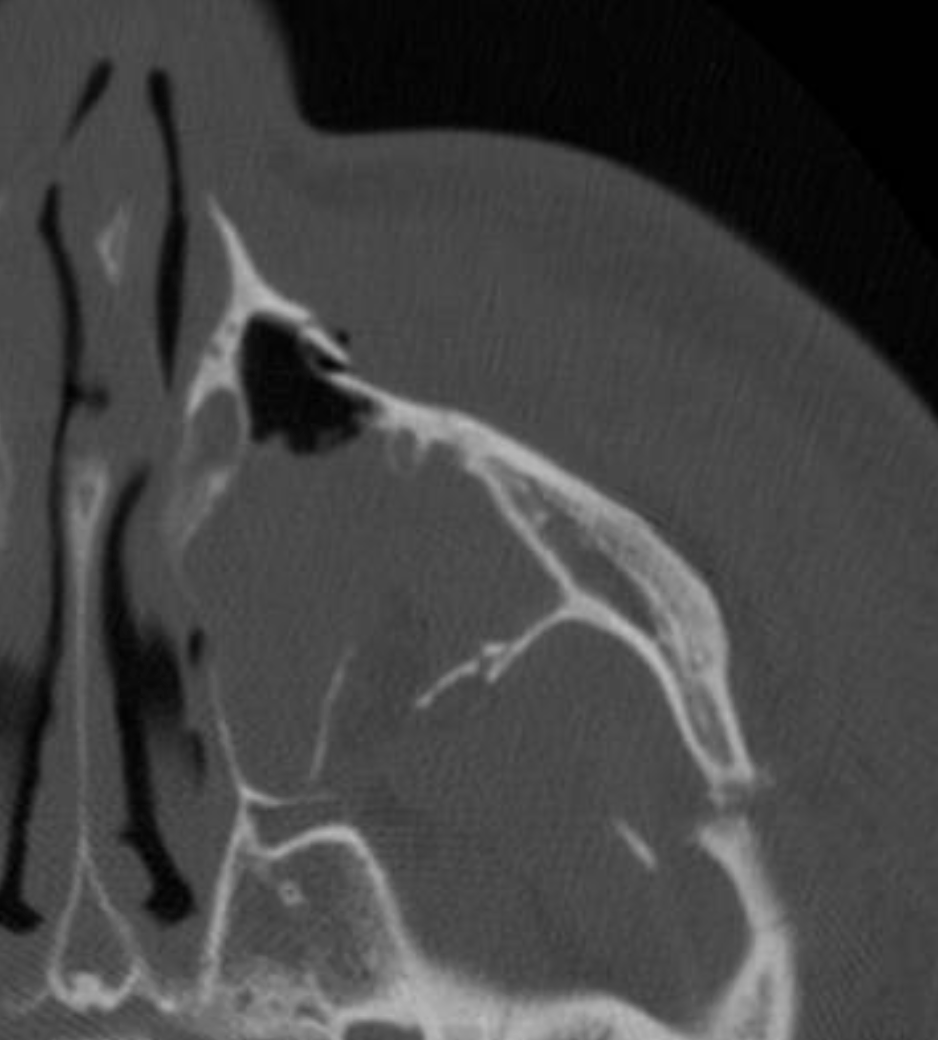

47M presents with multiple facial injuries following high impact car accident where he slammed the side of his chin/face into steering wheel. Endorses malocclusion. CT max face shows medial displacement of condyle.

Where does he most likely have fractures? In what order should they be repaired and how?

R condylar neck fx and L mandibular body or parasymphysis fx

First, you place pt in pre-morbid occlusion with arch bars and MMF. Then, you repair fx's within dental arch, moving anterior to posterior to guarantee proper occlusion. At the end, you reduce edentulous fractures (ie. condyle)

Can use 1 monocortical mini plate (2.0mm) per fracture making sure to have 3 holes on each side.

**studies no longer support needing rigid fixation of one of the fractures (with 2 mini plates, locking plate or 2.0 recon plate) - https://pubmed.ncbi.nlm.nih.gov/37772893/

Then you can treat the condylar neck fracture with MMF for 2 weeks or fixate it with 1-2x 2.0mm miniplates depending on height of fx.